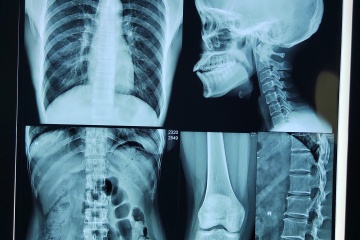

يُحدث الفيلم الحراري الجاف الطبي نقلة نوعية في قطاع التشخيص الطبي العالمي، إذ يُعدّ ركيزة أساسية في التصوير التشخيصي الحديث. يوفر هذا الفيلم وضوحًا فائقًا، ومتانة عالية، وسهولة في الاستخدام مقارنةً بوسائط التصوير التقليدية، مما يُمكّن مقدمي الرعاية الصحية من تعزيز دقة التشخيص، وتبسيط سير العمل، وتحسين نتائج رعاية المرضى. وقد ساهمت التطورات الحديثة في إنتاج الفيلم الحراري الجاف الطبي، مثل تحسين تركيب المواد وتقنيات الطلاء، في تعزيز دقة الصورة وثباتها أثناء التخزين. وبفضل طبقة الطلاء الحساسة للحرارة، يُنتج الفيلم صورًا عالية الجودة فورًا دون استخدام مواد كيميائية ضارة، مما يُقلل وقت المعالجة لاتخاذ قرارات سريرية سريعة. علاوة على ذلك، يشهد سوق الفيلم الحراري الجاف الطبي نموًا قويًا، مدفوعًا بتزايد الأمراض المزمنة وتزايد عدد كبار السن الذين يحتاجون إلى تصوير تشخيصي متكرر، مما يُعزز دوره المحوري في الرعاية الصحية.